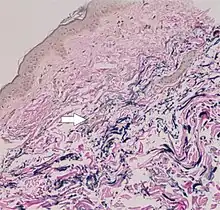

The diagnostic criteria for PXE are the typical skin biopsy appearance and the presence of angioid streaks in the retina. Criteria were established by consensus of clinicians and researchers at the 2010 biennial research meeting of the PXE Research Consortium.[29] and confirmed at the 2014 meeting[30] These consensus criteria state that definitive PXE is characterized by two pathogenic mutations in the ABCC6 or ocular findings – angioid streaks > 1 DD or peau d’orange in an individual <20 years of age together with skin findings:

- Diagnostic histopathological changes in lesional skin: Calcified elastic fibers in the mid and lower dermis, confirmed by positive calcium stain

| Pseudoxanthoma elasticum | LM: Mid-dermal calcification and fragmentation of elastic fibers EM: Mineralization in elastic fiber core |